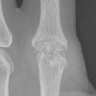

But his left " pointing finger" is a "0" and it looks very bad.

If you ask me they are swapped.

Which is pretty bad since there are so few "5" labels already.

Left (0-label)